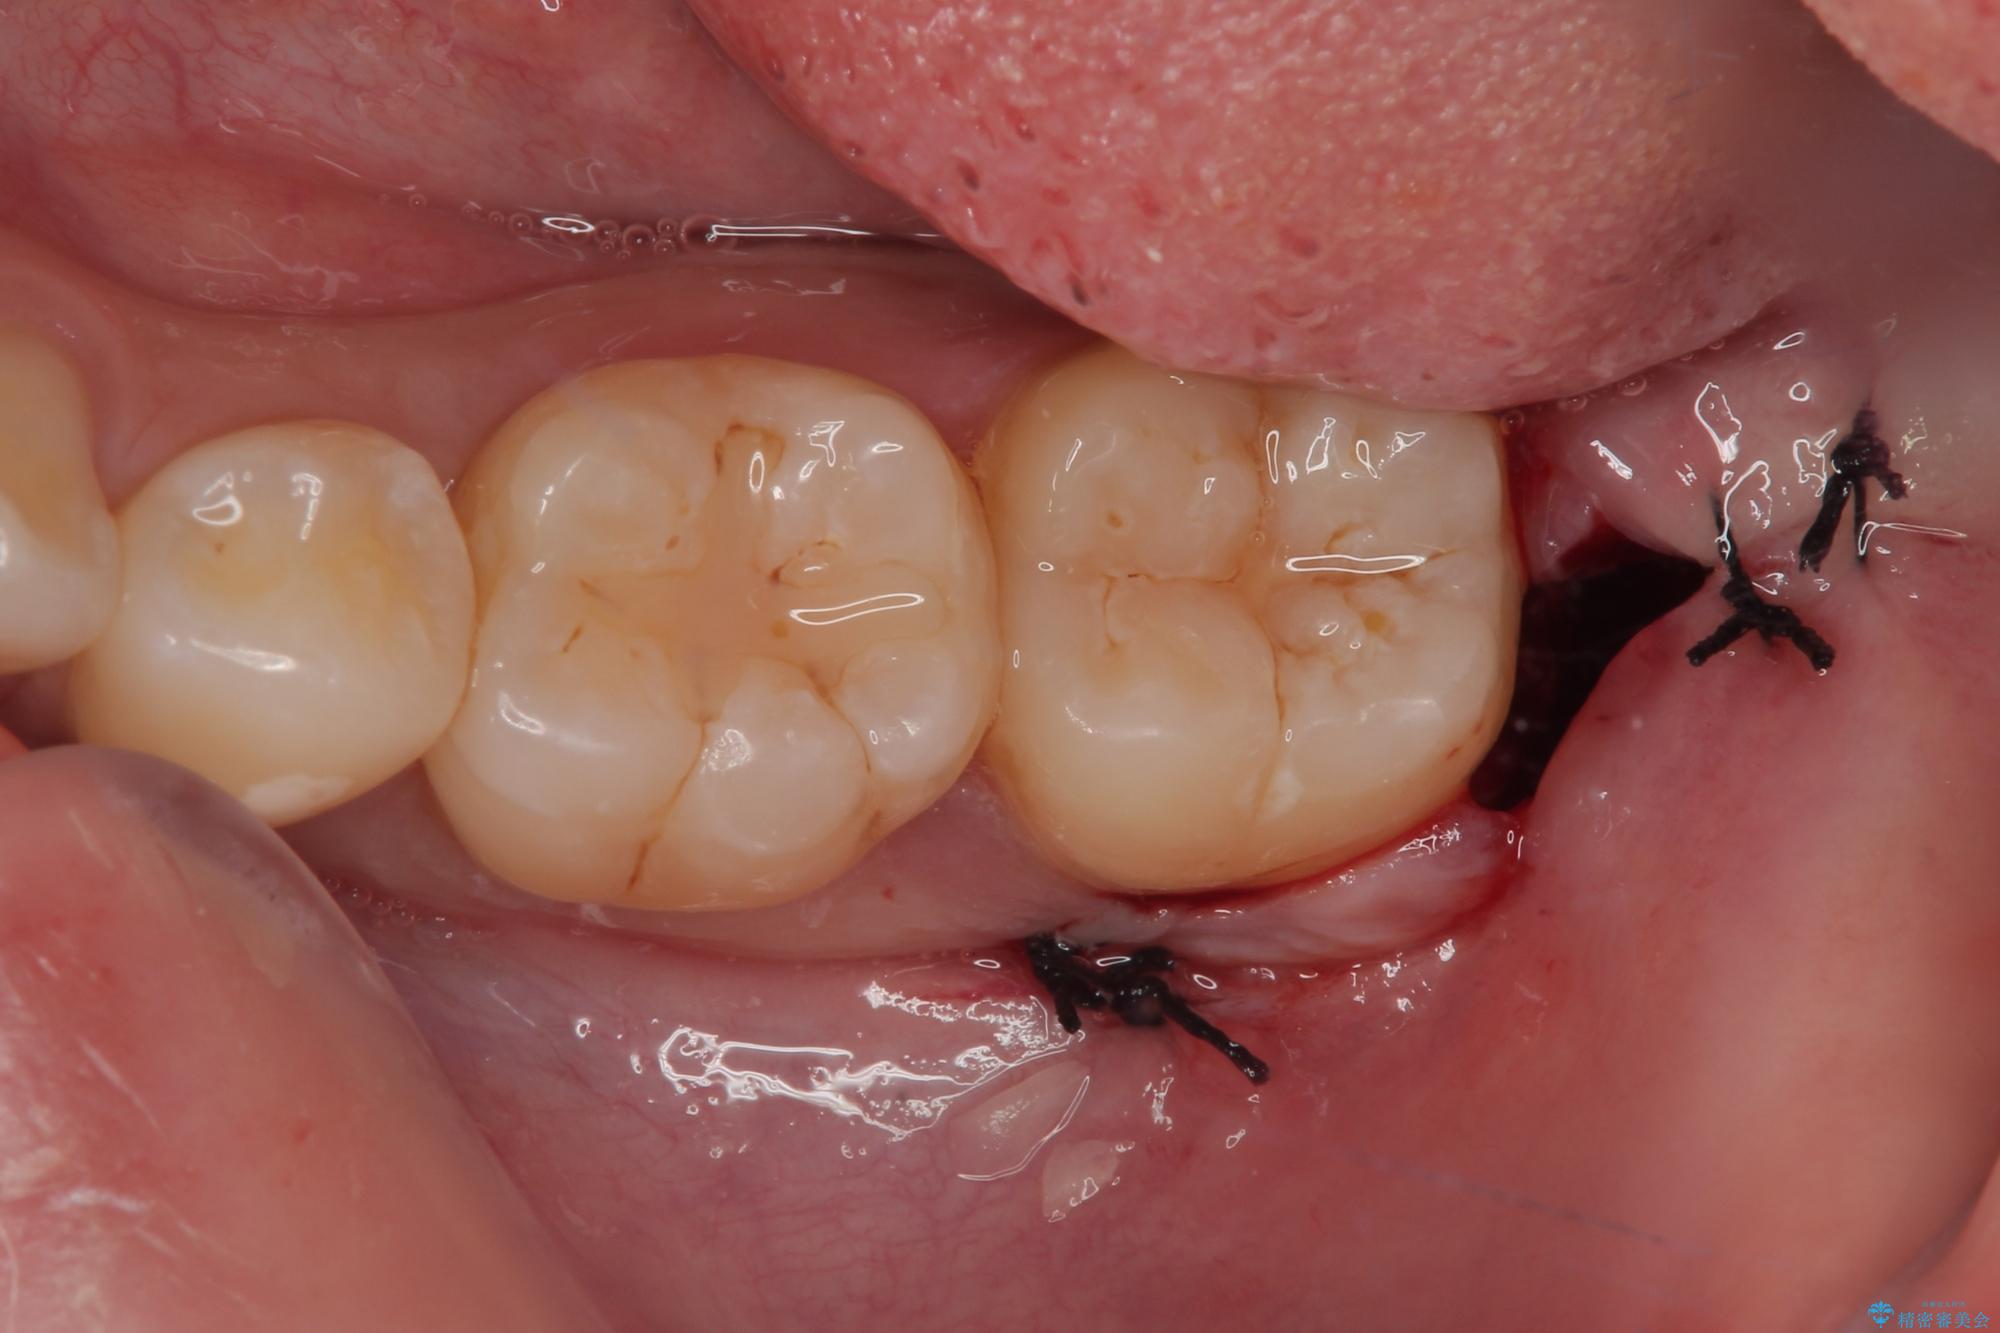

一週間後に抜糸を行いました。

しっかり麻酔が効いたことを確認してから安全に抜歯を行いました。